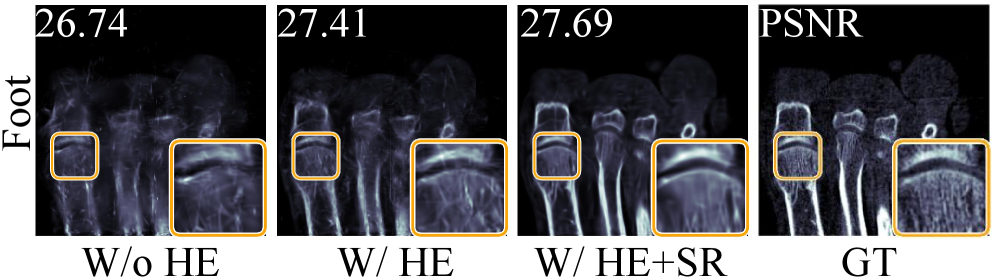

Refer to caption

Figure 3: Ablation of the hash encoder (HE) and semantic regularization (SR) on static CT reconstruction.

Component Analysis. We perform ablations on both static and dynamic CT to quantify the contribution of each module in TG-Field, including the hash encoder (HE), spatiotemporal attention block (STAB), motion-flow module (MF), and semantic regularization (SR). As summarized in Table 3, on static CT adding SR on top of HE brings a consistent gain in PSNR/SSIM, which is also reflected by sharper bone boundaries and fewer artifacts in Figure 3. On 4D CT, progressively introducing STAB and MF yields steady improvements, and the full model with SR achieves the best overall PSNR and SSIM. Qualitative results in Figure 5 further show that MF mainly refines motion-sensitive regions.